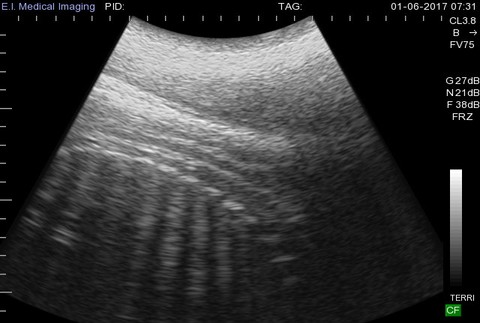

Malý hrošík je potomkom 17-ročnej hrošice Bibi a jej 35-ročného partnera Henryho. Zaujímavosťou je, že hrošík bol úplne prvým v histórii, ktorého nasnímali ešte v maternici ultrazvukom (foto v galérii). Gravidita hrocha, ktorý môže v dospelosti vážiť až štyri tony, trvá zhruba 8 mesiacov, čo je na také veľké zviera pomerne málo. Pre porovnanie gravidita nosorožcov trvá 15 mesiacov a slonov až 22 mesiacov.